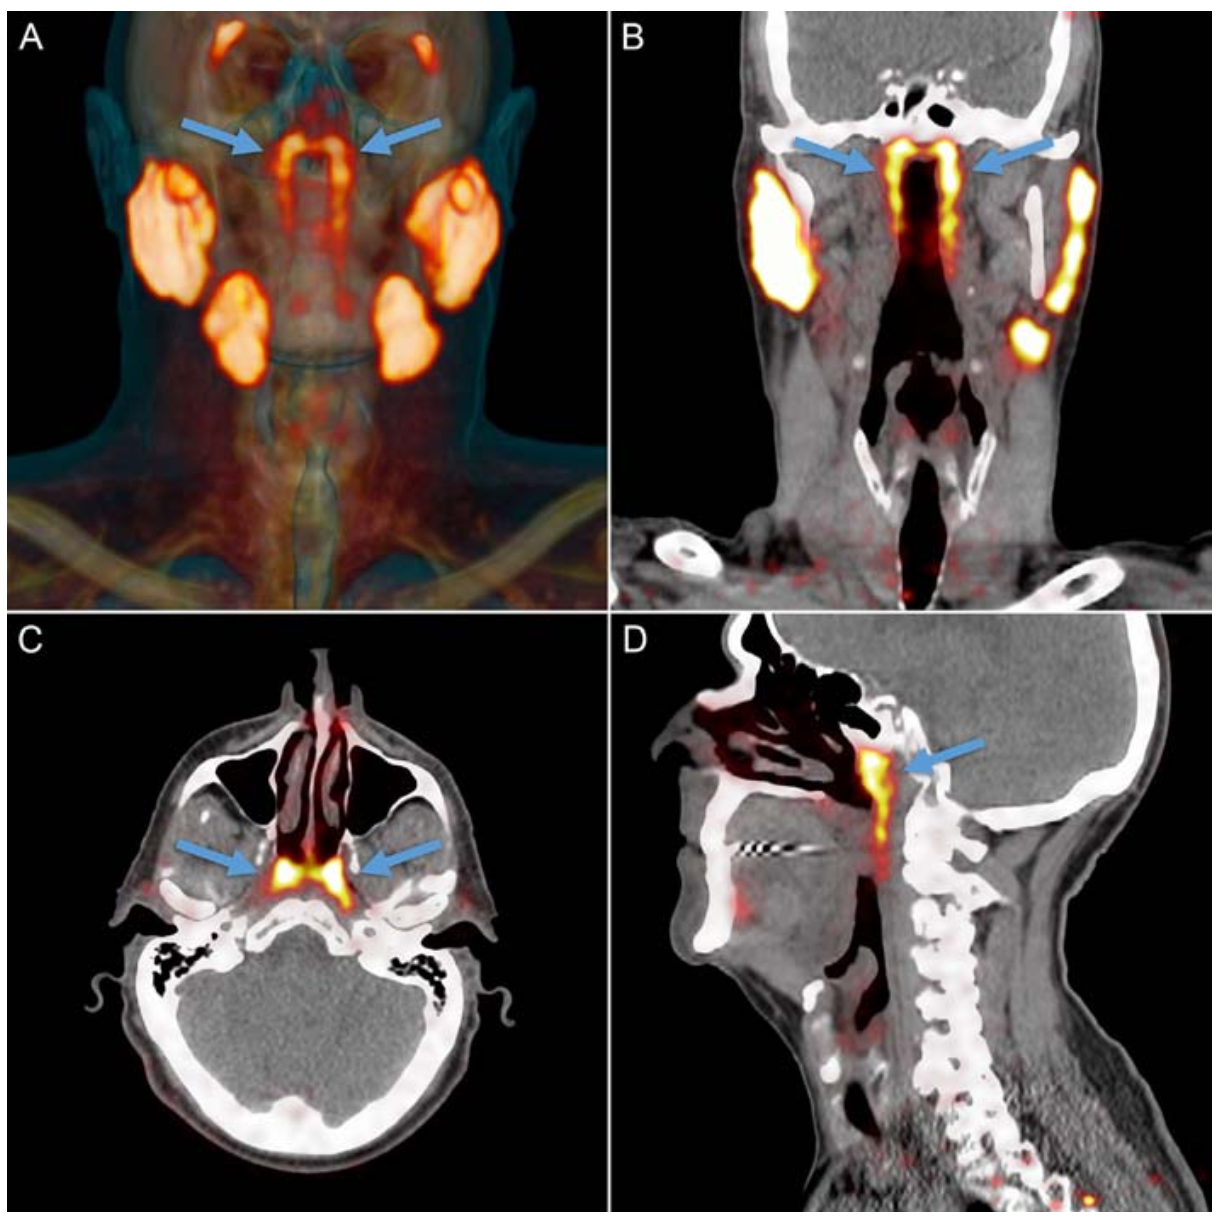

빠르게 변하고 있는 시대 속에서 이를 따라가기 위해서는 지속적인 노력이 필요합니다. 그리고 최근 해부학 교과서가 바뀌는 새로운 발견이 있었습니다. 새롭게 발견된 해부학적 구조물은 바로 '침샘'이었습니다.

'침샘은 소화 기관에 필요한 타액을 생산하는 곳으로 육안으로 확인할 수 있는 침샘은 크게 귀밑샘, 턱밑샘, 혀밑샘 이렇게 3개가 존재하고 있습니다.' 이것이 기존의 우리들의 지식이었고 상식이었으며, 교과서의 정석이였습니다. 하지만 이 내용은 이제 바뀌게 됩니다.

2021년 Matthijs 외 연구진은 유연히 CT장비를 통해 해부학적으로 새로운 발견을 했습니다. 이 침샘은 이관융기(torus tubarius)라고 하는 연골 위쪽에 위치하고 있었기 때문에 'tubarial salivary glands'라는 이름이 붙게 되었습니다. 이 침샘은 현재의 해부학 교과서에 없는 완전히 새로운 해부학적 구조물이기 때문에 조만간 해부학 교과서가 바뀌게 될 예정입니다.

이 발견이 주는 의미는 1970년대부터 CT 촬영이 시작된 이례로 약 50년이 지난 후에 찾아낸 새로운 발견이었다는 겁니다. 새롭게 발견된 침샘의 평균 크기는 3.9cm에 달하는 커다란 침샘이라는 점에서 과학자들은 이렇게 커다란 침샘을 지난 50년 동안 발견하지 못했다는 점에서 충격을 받은 하나의 사건이었습니다.